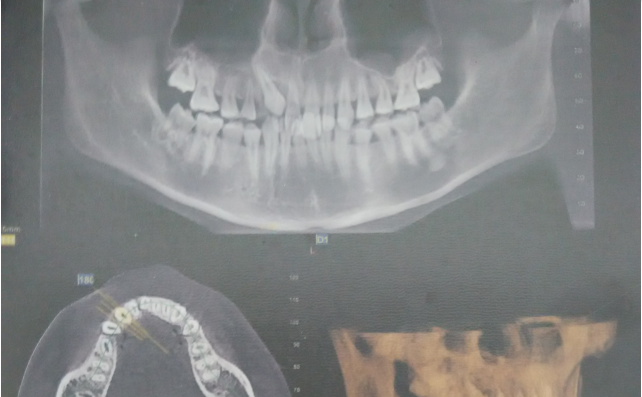

圖6.術(shù)前CBCT影像檢查:13位于腭側(cè)。準(zhǔn)確定位,為下一步切除牙齦組織打好基礎(chǔ)。